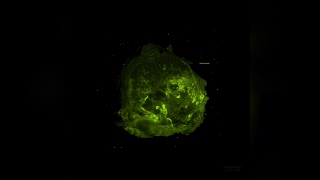

A virtual reality journey through a tumour video

A virtual reality journey through a tumour

A virtual reality journey through a tumour